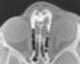

Midline dermoid

Dermoid sinus is a thought to be a genetic skin condition in dogs. It is also known as pilonidal sinus. [Source: Wikipedia ]